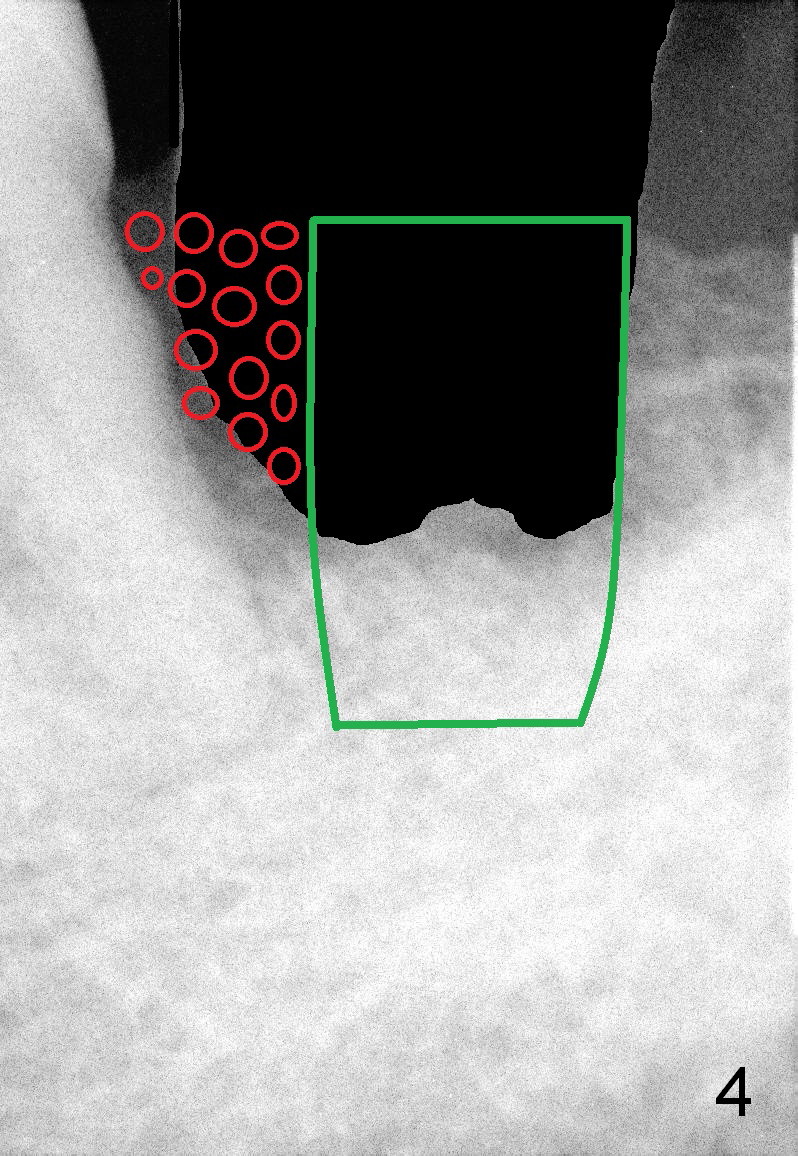

A 63-year-old man has periodontitis. The tooth #18 (probably 17) has mobility III (Fig.1). Three more PAs are taken with deeper placement of #2 sensor (Fig.2,6,7) to show the upper border of the Inferior Alveolar Canal (yellow dashed lines). The affected tooth has severe bone loss, especially mesially (Fig.2,3 (arrowheads)). No matter whether bone (Fig.4) or gingiva (Fig.5)-level implant is placed, the threads should be covered circumferentially by bone, native or grafted (red circles). In Fig.5, the threads are apical to black arrowheads, whereas the rough surface, which should be also contacted by bone, is the lower half above the black arrowheads.